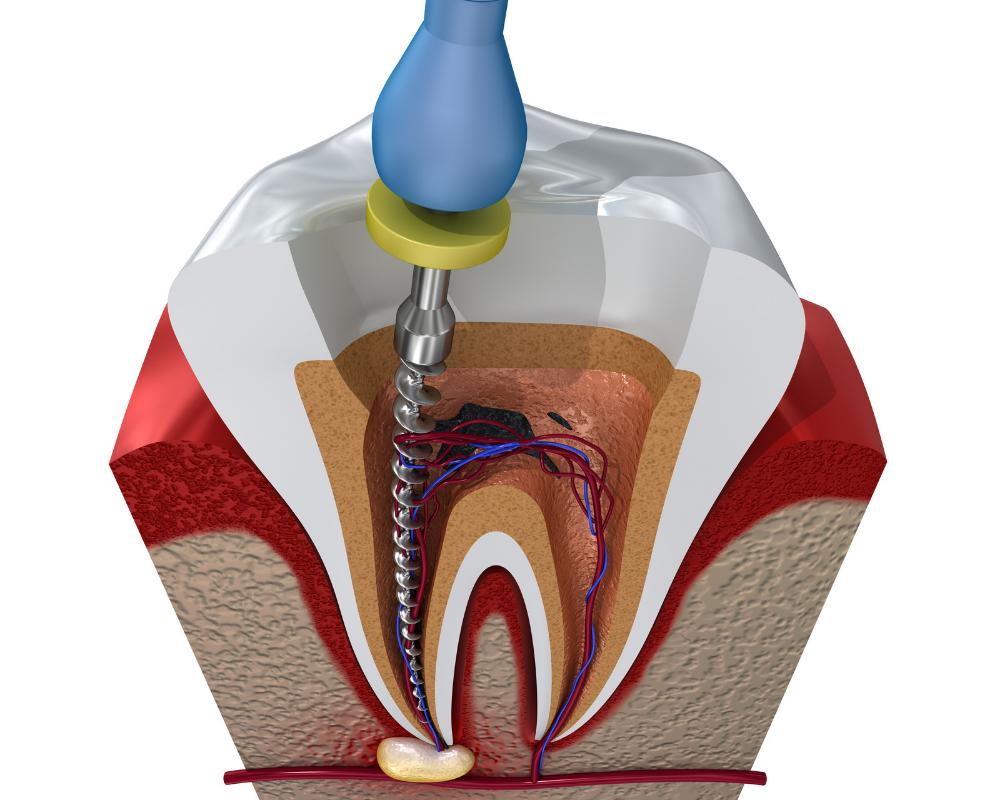

Root Canal Treatment

Root Canal Treatment is a procedure performed on the infected tooth to remove the decay affecting the pulp (underlying tissue containing blood vessels and nerve supply to a tooth). Simple filling procedure cannot restore a tooth’s dental health when the infection has encroached the pulp. Root canal therapy is the only alternative to save such tooth from being extracted. The main objective of root canal treatment is to preserve the infected existing natural tooth by disinfection. During a root canal therapy, access to the root canal present inside the root of a tooth is gained and the infected tissue is removed entirely. Hence Root Canal treatment bypasses extraction of the infected tooth and its replacement procedures thereby saving time and money.